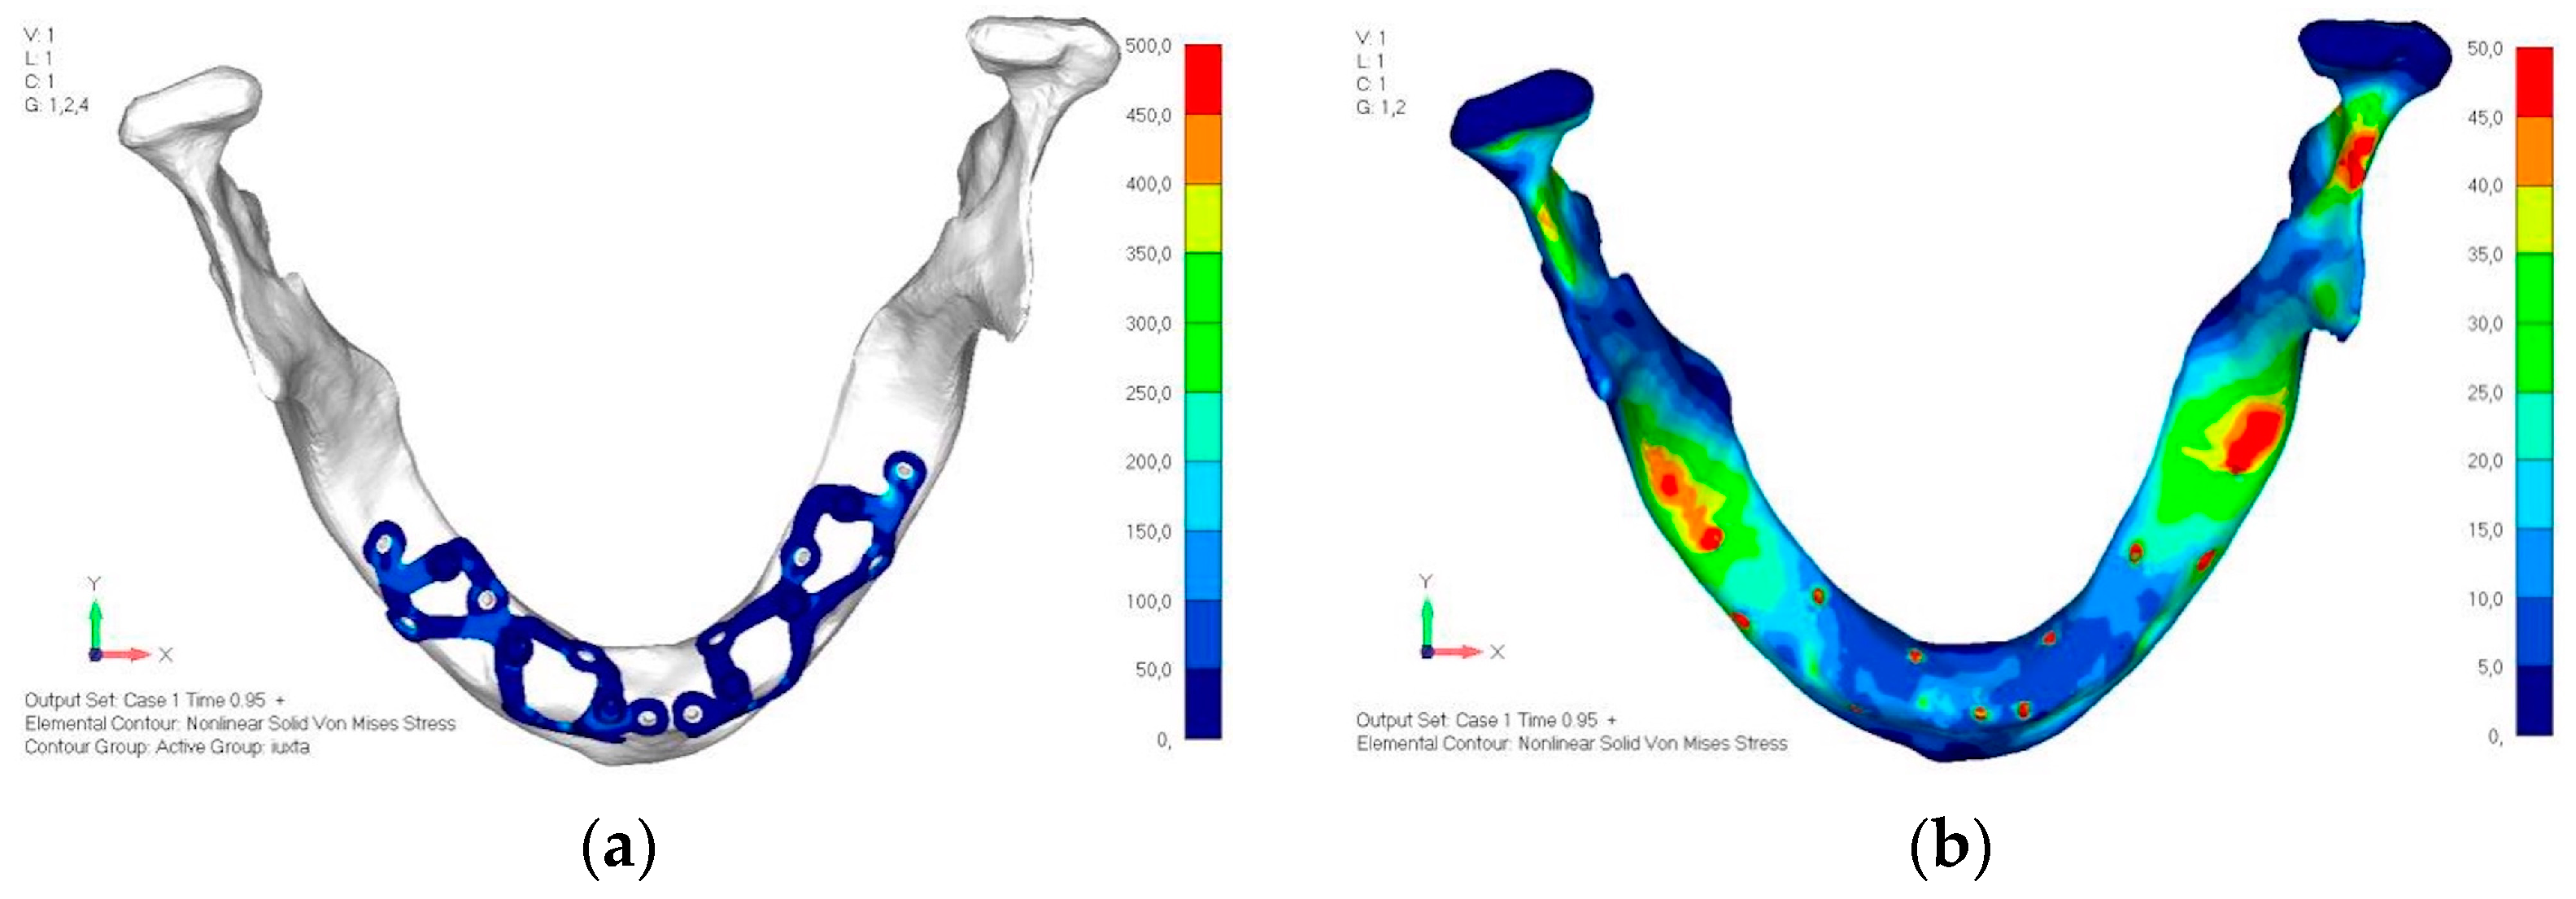

- Model V5. This version of the implant retains the same geometry as version 4, with the addition of two connecting bars, one on the lingual side and one on the vestibular side (Figure 31). The purpose of this analysis is to identify the differences between a monolithic implant and an implant divided into two hemi-arches. The results are quite similar to those observed in the upper model: the presence of a connection between the two halves of the implant does not contribute to its stability. It is immediately noticeable that the two connecting bars exhibit stresses close to 0, indicating that no force is transmitted through them (Figure 32a,b). Once again, a significant contribution is provided by the prosthesis, which stiffens the structure through the abutments.